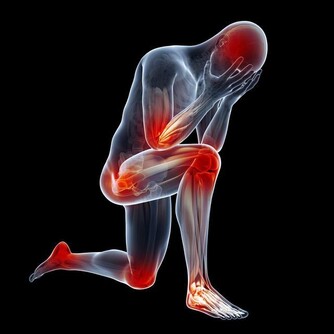

四肢常常抽筋

這也許是缺鈣和維生素D。它們決定骨骼的硬度和肌肉的縮短。要多吃些奶製品、肝臟、海鮮。